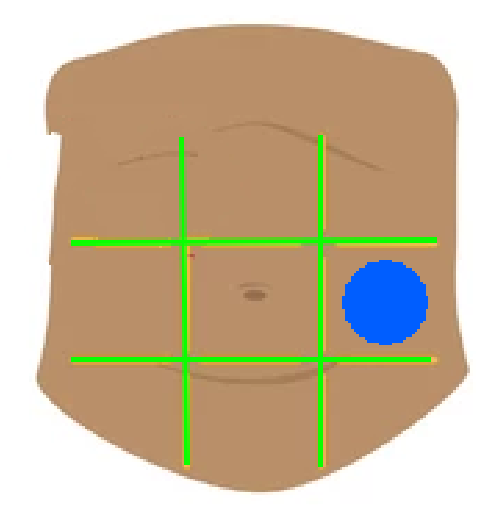

Right hypochondriac region

Left hypochondriac region

Epigastric region

Right lumbar region

Left lumbar region

Umbilical region

Right inguinal region

Left inguinal region

Hypogastric regions